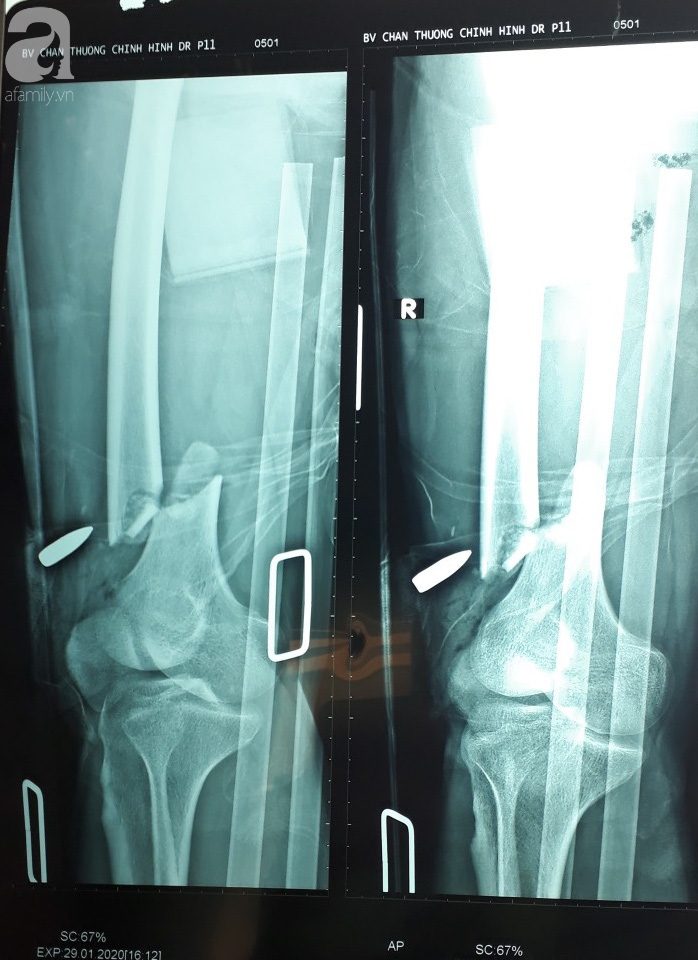

Tối 1/2, một nguồn tin tại Bệnh viện (BV) Chấn thương chỉnh hình TP.HCM cho biết, anh Trần Văn T. (32 tuổi), một trong các nạn nhân bị bắn tại sòng bạc xã Tân Thạnh Đông (huyện Củ Chi, TP.HCM) ngày 29/1 vẫn đang điều trị tại khoa Chi dưới của BV.

Trước đó, anh T. nhập viện trong tình trạng gãy hở nát 1/3 xương đùi trái, vết thương dập nát ở đùi phải do đạn bắn, đứt gân cơ từ đầu đùi và nhiều mảnh xương đùi gãy.

Các bác sĩ trực khoa Chi dưới đã tiến hành lấy viên đạn ra khỏi đùi và mổ cắt lọc vết thương, nối gân cơ đùi. Sau mổ, sức khoẻ bệnh nhân tiến triển tốt và đang được xuyên đinh kéo tạ.

Khi vết thương tiến triển tốt, bệnh nhân sẽ được kết hợp xương bên trong.